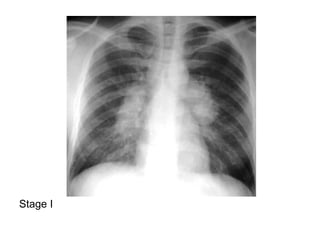

2-Classification :

-May be classified on a chest radiograph into 5

stages :

Stage 0 : normal chest radiograph

Stage I : hilar or mediastinal nodal enlargement

only

Stage II : nodal enlargement and parenchymal

disease

Stage III : parenchymal disease only

Stage IV : end-stage lung (pulmonary fibrosis)

Stage I